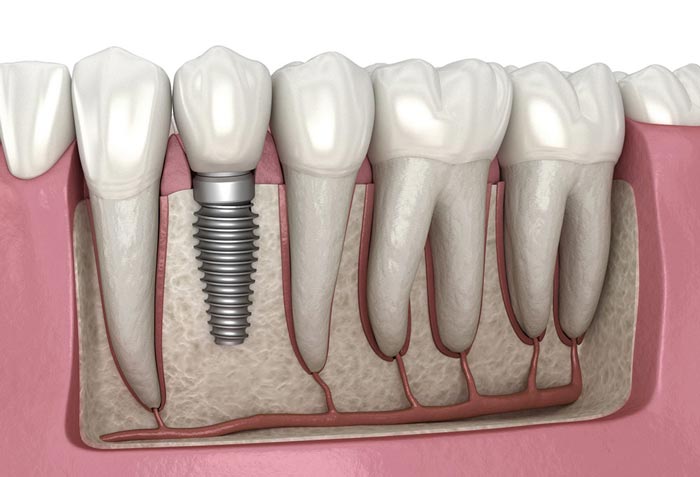

کاشت دندان

اگر به دنبال روشی پیشرفته و دائمی برای جایگزینی دندان های از دست رفته هستید، کاشت یا همان ایمپلنت دندان بهترین گزینه است. در این روش، یک پایه فلزی (معمولاً تیتانیوم یا زیرکونیوم) درون استخوان فک قرار میگیرد. پس از طی شدن دوره ای برای جوش خوردن پایه به استخوان (اُسیواینتگریشن)، یک روکش سفارشی روی پایه نصب میشود. این روکش دندان کاملاً مشابه دندان طبیعی بوده و عملکردی مشابه آن دارد.

ایمپلنت به طور ویژه برای کسانی که به دنبال راه حلی بادوام هستند مناسب است، اما هزینه بالای آن ممکن است برای برخی محدودیت ایجاد کند. با این حال، مزایای آن از جمله جلوگیری از تحلیل استخوان فک و حس طبیعی در جویدن، آن را به انتخابی محبوب تبدیل کرده است. دکتر امیر بهرامی بهترین دکتر ایمپلنت در تهران است که سالها در این زمینه تخصص و تبحر دارد. شما عزیزان می توانید جایگزینی دندان از دست رفته خود را با ایمپلنت و توسط دکتر امیر بهرامی در کلینیک تریدنتال انجام دهید. برای مشاهده قیمت ایمپلنت دندان و عوامل تاثیر گذار بر آن روی این لینک کلیک کنید.

ایمپلنت دندان یکی از بهترین روشها برای پر کردن جای خالی دندان کشیده شده است. در این روش، یک پیچ فلزی به جای ریشه دندان در استخوان فک کاشته میشود و پس از آن، یک تاج دندانی بر روی آن نصب میشود. ایمپلنت نه تنها ظاهر طبیعی دندان را به فرد باز میگرداند، بلکه به حفظ سلامت استخوان فک نیز کمک میکند. علاوه بر ایمپلنت، روشهای دیگری مانند بریج دندانی و دندانهای مصنوعی نیز وجود دارند که میتوانند به جای دندان کشیده شده استفاده شوند، هرچند ممکن است نیاز به دندانهای مجاور یا زمان بیشتری برای تطبیق داشته باشند.

جایگزینی دندان از دست رفته یکی از چالشهای رایج در دندانپزشکی است که روشهای مختلفی برای آن وجود دارد. یکی از بهترین و محبوبترین روشها، کاشت دندان یا ایمپلنت است که در آن یک پایه فلزی در فک قرار میگیرد و تاج دندان به آن متصل میشود. این روش نه تنها ظاهر طبیعی دندان را بازمیگرداند بلکه عملکردی مشابه دندانهای طبیعی نیز دارد. روش دیگر پروتزهای دندانی هستند که میتوانند به صورت دندان های مصنوعی ثابت یا متحرک تهیه شوند. بریج دندان، یکی دیگر از گزینهها است که با استفاده از دندانهای سالم مجاور، یک پل برای جایگزینی دندان از دست رفته ایجاد میکند. در نهایت، دندانپزشکان بسته به وضعیت فک و دندانهای بیمار، هر یک از این روشها را پیشنهاد میدهند تا بیمار بتواند بهترین انتخاب را بر اساس نیازهای خود داشته باشد.